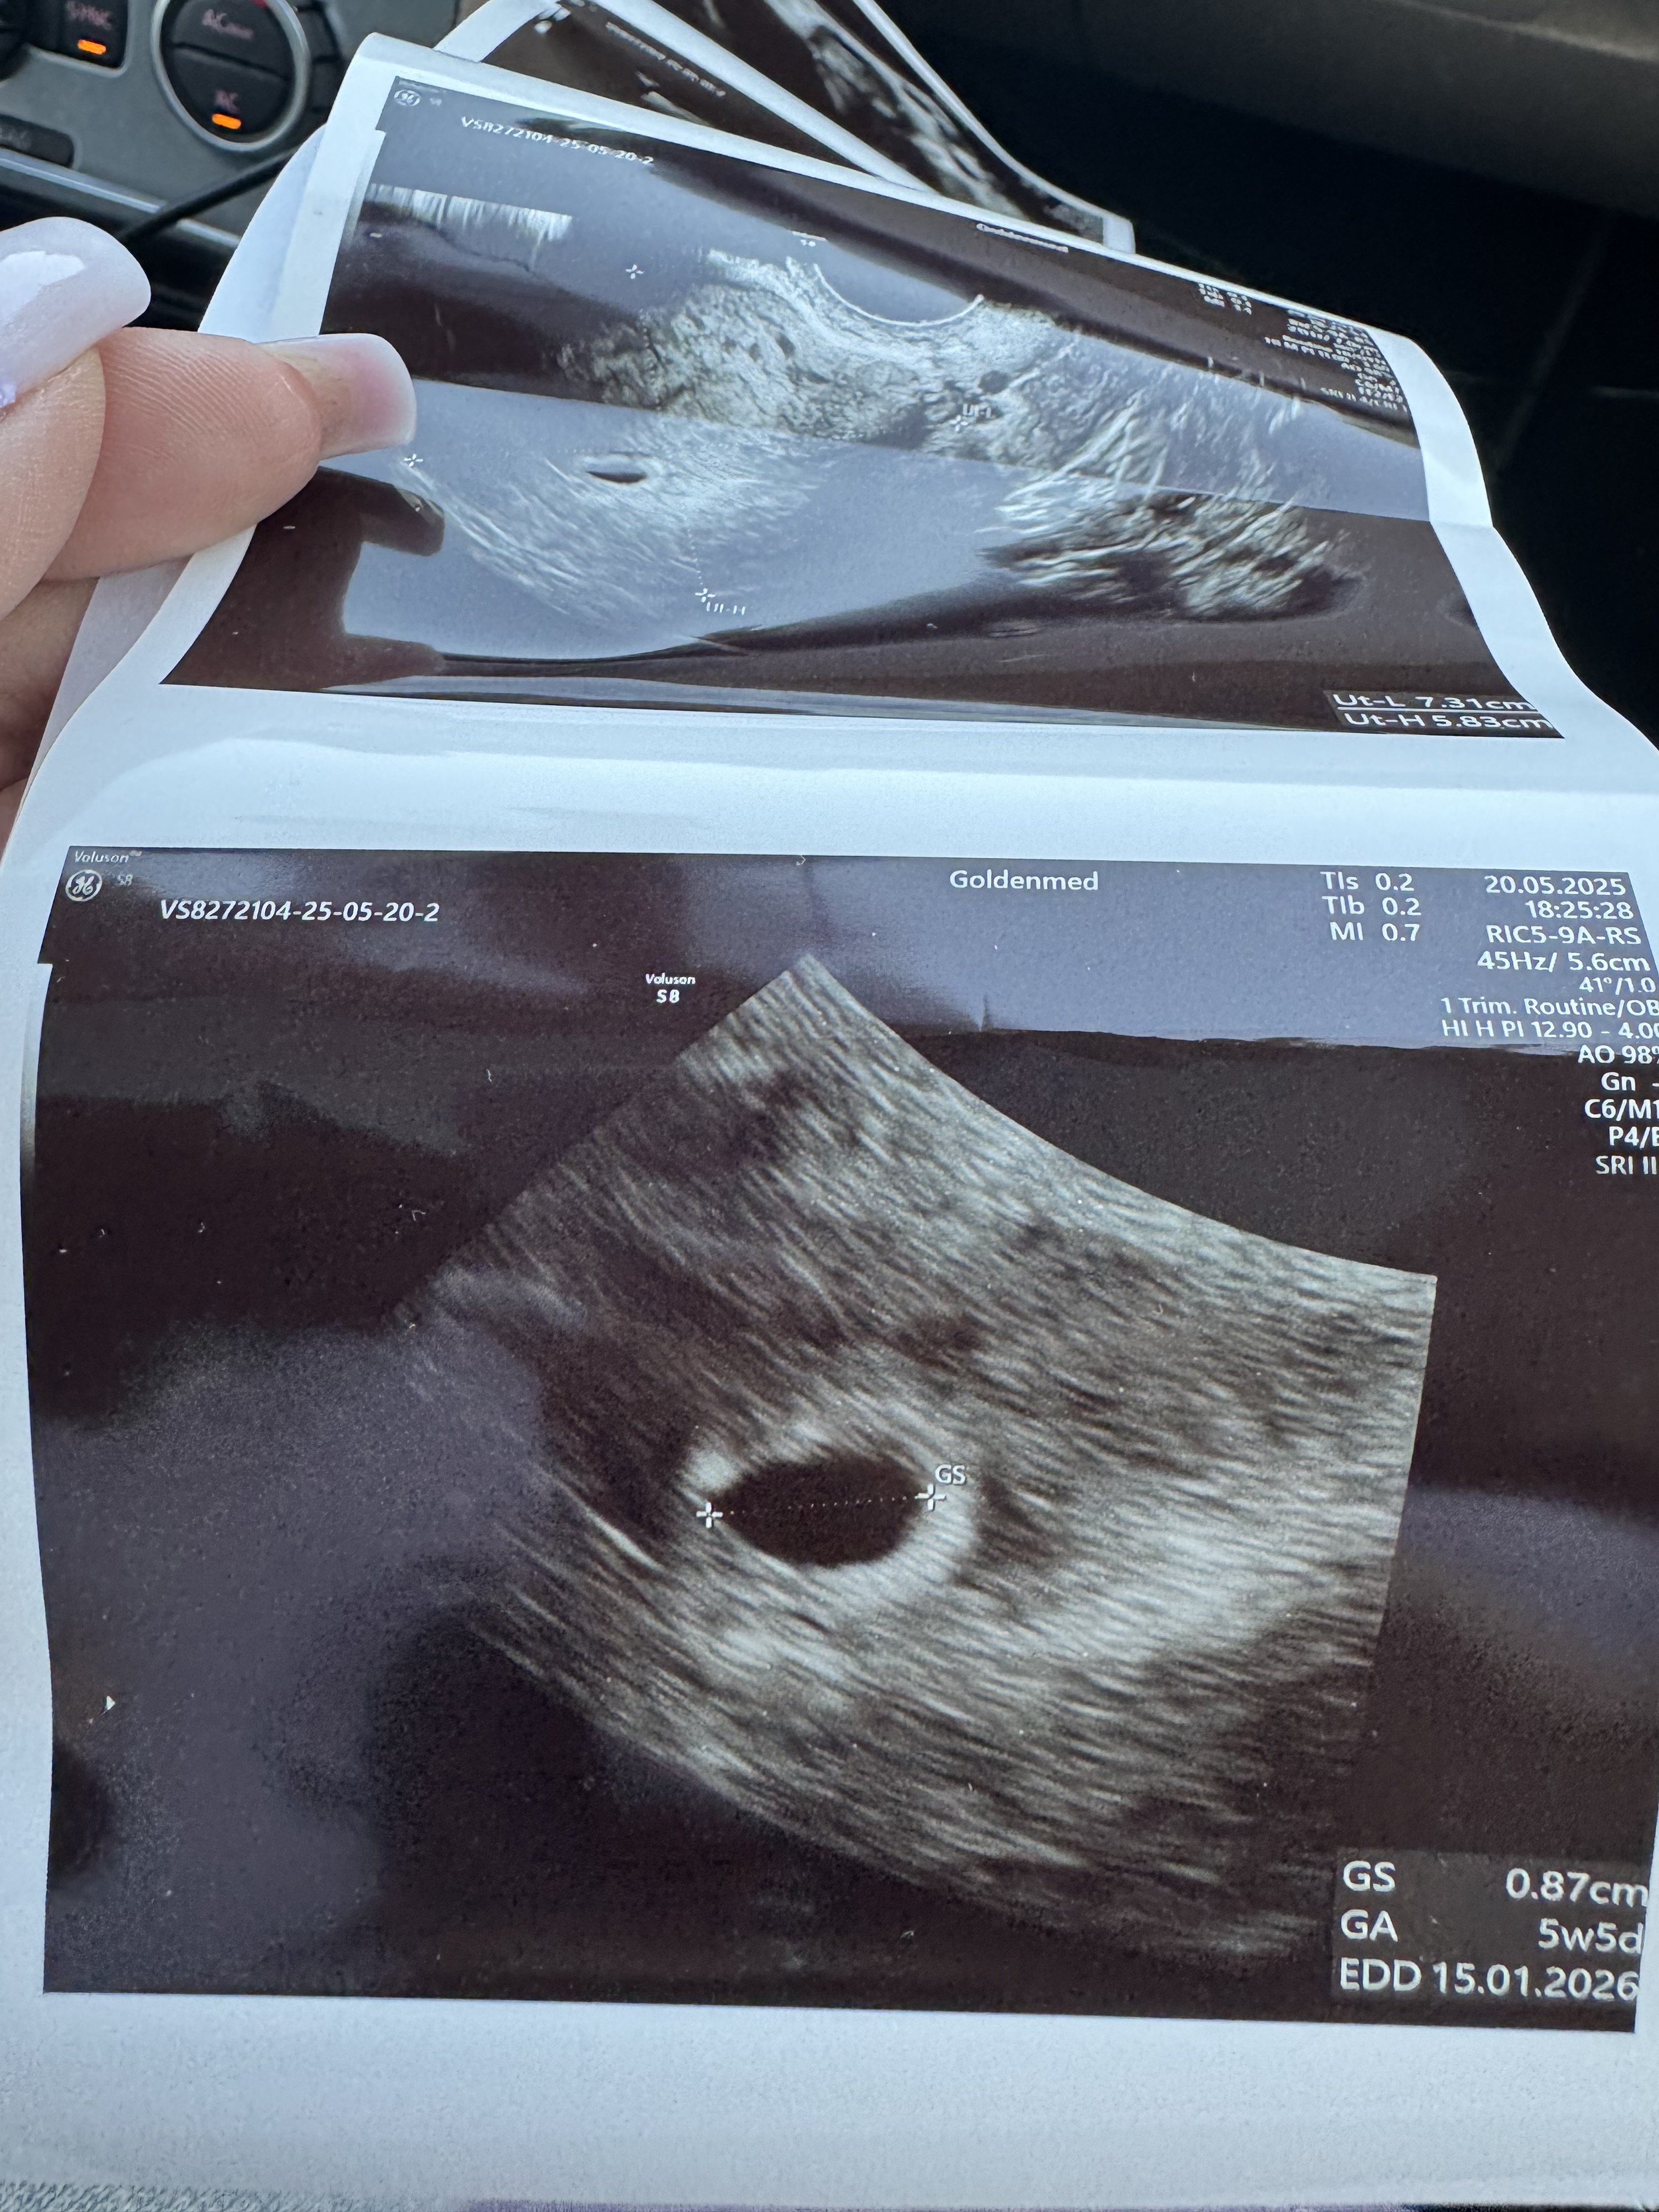

Jestem po wizycie. Jest pęcherzyk ciążowy narazie pusty, umiejscowiony prawidłowo. Za 2 tyg mam znów USG zrobić by zobaczyć czy będzie pęcherzyk z zawartością. Beta przyrasta prawidłowo. Wielkość pęcherzyka odpowiada 5+5

• IMG_1685.jpeg

1,5 MB · Wyświetleń: 98